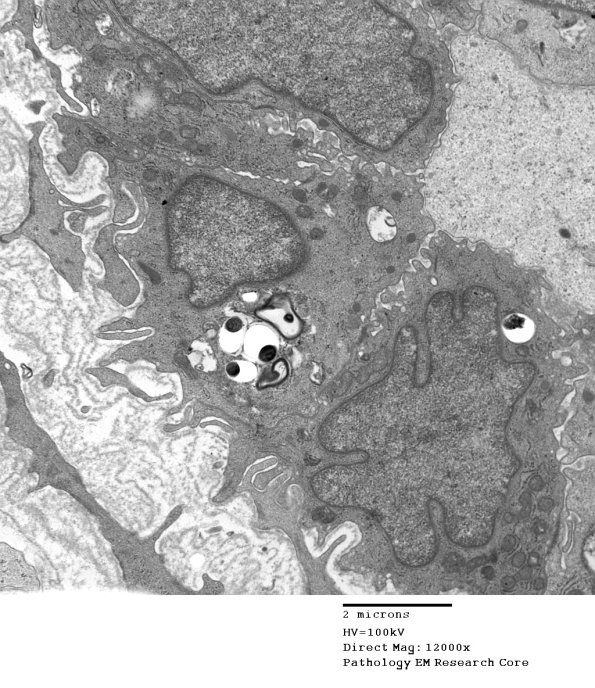

Leprous organisms infect the endothelium. Diseased endothelial cells may appear swollen, with loss of integrity of cell junctions and other signs of damage to the blood–nerve barrier. Multilayering and thickening of basement membrane around vessels is seen in all types of leprosy but it is a nonspecific finding in many chronic neuropathies. (electron micrographs)